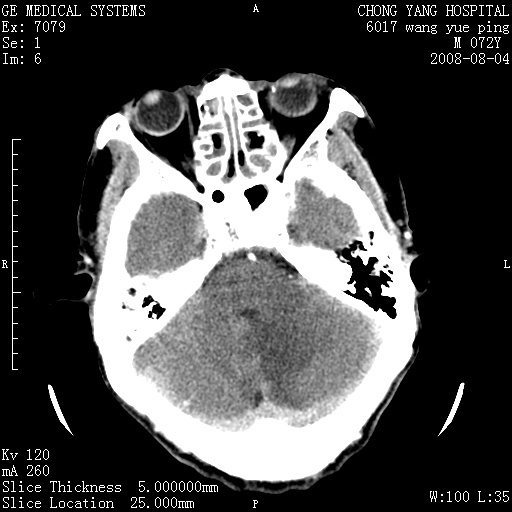

标题: CT14987:M72Y,头痛头昏,BP220/110. [打印本页]

1)考虑左侧小脑脑梗塞。2)脑白质病。3)脑萎缩。4)双侧鼻腔新生物(息肉?)并阻塞性副鼻窦炎。

1.左侧小脑大面积梗塞;2.左侧基底节区腔梗;3.白质疏松;4.脑萎缩;5.慢性副鼻窦炎

小脑左侧病灶呈扇形分布,增强后未见明显瘤体样节结影,病变区未见强化。

支持:左侧小脑脑梗塞梗塞表现

另:脑白质病。脑萎缩。双侧鼻腔新生物(息肉?)并阻塞性副鼻窦炎。

1)考虑左侧小脑脑梗塞,建议治疗后复查除外其他,左基底节区腔隙性脑梗塞2)脑白质变性3)脑萎缩。4)双侧鼻腔新生物(息肉?)并阻塞性副鼻窦炎。